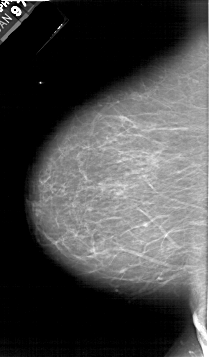

A_1615_1.RIGHT_MLO

RIGHT_MLO LINES 6406 PIXELS_PER_LINE 3931 BITS_PER_PIXEL 12 RESOLUTION 43.5 OVERLAY

FILE: A_1615_1.RIGHT_MLO.OVERLAY

TOTAL_ABNORMALITIES 1

ABNORMALITY 1

LESION_TYPE MASS SHAPE LOBULATED MARGINS CIRCUMSCRIBED

ASSESSMENT 4

SUBTLETY 5

PATHOLOGY BENIGN